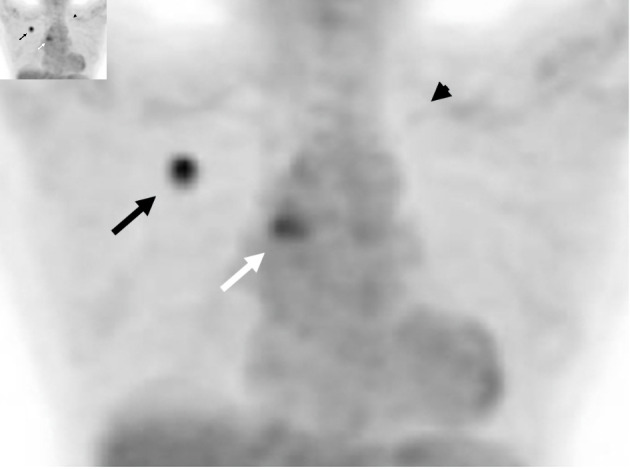

在非小细胞肺癌中发现并开发了各种驱动突变和相应的分子靶向药物。手术标本中发现双原发癌的病例很多。然而,据我们所知,我们的病例是首次报告同步双原发性肺腺癌,且表皮生长因子受体(EGFR)L858R和间质-上皮转化(MET)第14外显子跳越突变。一名 75 岁的日本妇女因胸部 X 光片显示右上肺野有一个不断增大的结节而被转诊至我科,她患有慢性心衰和肾衰竭。胸部计算机断层扫描(CT)发现右侧 S1 肺部有一个结节,左侧 S1+2 肺部也有一个结节。支气管镜活检诊断右侧 S1 结节为中度分化腺癌。右侧 S1 腺癌的 Oncomine Dx Target Test Multi-CDx 系统检测到表皮生长因子受体 L858R 突变。18F-氟脱氧葡萄糖正电子发射断层扫描/CT显示右侧S1和左侧S1+2结节以及双侧气管旁下淋巴结均有异常摄取。我们诊断她的右侧 S1 结节为 c 期 IIIA(cT1bN2M0)腺癌,并怀疑左侧 S1+2 结节为另一种原发性肺癌。考虑到她的一般情况、合并症和意愿,我们开始使用奥希替尼。右侧 S1 癌症取得了部分反应(PR),而左侧 S1+2 结节和淋巴结肿大。左锁骨上淋巴结的抽吸细胞学检查显示为腺癌。FoundationOne® Liquid CDx肿瘤图谱检测不仅发现了表皮生长因子受体(EGFR)L858R,还发现了MET第14外显子跳跃突变。我们诊断左侧S1+2结节为另一种原发性腺癌(cT1bN3M0,c期IIIB),且伴有MET突变,并将奥希替尼改为卡马替尼。虽然左侧 S1+2 癌症通过卡马替尼达到并维持了 PR,但右侧 S1 癌症却有所增加,并出现了几个新的转移灶。随后将卡马替尼换成了奥希替尼,但仍无法控制癌症。在这种情况下,我们尝试根据每种癌症的进展情况,将携带不同两种驱动突变的双原发性腺癌的单一疗法从奥希替尼切换到卡马替尼。时间和空间异质性加强了在怀疑双原发时进行原发组织活检的必要性。可以考虑进行目前尚不规范的不同时间的液体活检。

Various driver mutations and the corresponding molecular-targeted drugs have been detected and developed in non-small cell lung cancer. There were many cases in which surgical specimens had happened to find double primary cancers. However, to our knowledge, our case was the first report of synchronous double primary lung adenocarcinomas harboring epidermal growth factor receptor (EGFR) L858R and mesenchymal-to-epithelial transition (MET) exon 14 skipping mutations. A 75-year-old Japanese woman with chronic heart and renal failures was referred to our department because of a growing nodule in the right upper lung field on chest X-ray films. Chest computed tomography (CT) detected a nodule in the right S1 and another nodule in the left S1+2. Bronchoscopic biopsy diagnosed the right S1 nodule as moderately differentiated adenocarcinoma. Oncomine Dx Target Test Multi-CDx system of the right S1 adenocarcinoma detected EGFR L858R mutation. The 18F-fluorodeoxyglucose positron emission tomography/CT showed abnormal uptakes both in the right S1 and the left S1+2 nodules, and in the bilateral inferior paratracheal lymph nodes. We made a diagnosis of c-stage IIIA (cT1bN2M0) of adenocarcinoma in the right S1 and suspected another primary lung cancer in the left S1+2. Considering her general conditions, comorbidities and wishes, we started osimertinib. The right S1 cancer achieved partial response (PR), while the left S1+2 nodule and lymph nodes enlarged. Aspiration cytology from the left supraclavicular lymph node showed adenocarcinoma. The FoundationOne® Liquid CDx tumor profiling test detected not only EGFR L858R, but also MET exon 14 skipping mutation. We made a diagnosis of another primary adenocarcinoma from the left S1+2 nodule (cT1bN3M0, c-stage IIIB) with MET mutation, and changed osimertinib to capmatinib. Although the left S1+2 cancer achieved and maintained PR by capmatinib, the right S1 cancer increased, and several new metastases appeared. The subsequent switch from capmatinib to osimertinib could not control cancers. In this case, we tried to switch monotherapies from osimertinib to capmatinib for double primary adenocarcinomas harboring different two driver mutations, according to each cancer progression. The temporal and spatial heterogeneity reinforces the need for primary tissue biopsy if dual primaries are suspected. Temporally distinct liquid biopsies, not standard at present, may be considered.